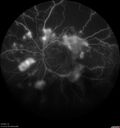

Severe Proliferative Diabetic Retinopathy and Good Vision

49 year old man with vision loss in the right eye for 2 weeks. VA 20/40 OD, 20/63 OS. DM x 15 years and HTN.